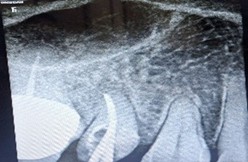

A 44-year-old woman presented to our dental department in May 2025 with a one-week history of a prominent left facial swelling extending from the corner of her mouth to the lower border of her left eyelid, accompanied by restricted eye opening. Her dental history was notable for a large amalgam restoration on tooth 26. Periapical radiography revealed an extensive radiolucent lesion associated with the palatal root of that tooth.

Three weeks post-treatment, the facial swelling had markedly diminished. Follow-up radiographs demonstrated progressive lesion regression, and at 2.5 months the periapical defect was largely replaced by healthy trabecular bone.

Figure 1: Pre operative IOPA revealing a huge periapical lesion wrt palatal root of 26.

Figure 4: Two and half months post op Xray after metapex placement reveals nearly complete resolution of periapical radiolucency.